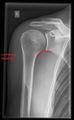

تصوير الكتف

أشعة إكس